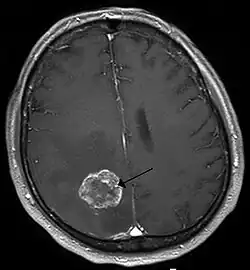

T1-gewichtete kontrastmittelverstärkte Magnetresonanztomografie einer Hirnmetastase eines Bronchialkarzinoms (linke Hirnhälfte, weißer kreisrunder Bereich)

Metastasierende Tumorzellen, speziell von Bronchialkarzinomen, Mammakarzinomen und malignen Melanomen, sind in der Lage die Blut-Hirn-Schranke zu überwinden und zerebrale Metastasen mit ausnahmslos schlechter Prognose zu bilden.[14] Bei etwa 20 bis 40 % aller Krebspatienten bilden sich Hirnmetastasen.[84] Bei der Migration dieser Zellen in das Zentralnervensystem spielt ebenfalls der Vascular Endothelial Growth Factor. (VEGF) eine wichtige Rolle. VEGF wird von Mammakarzinom-Zellen[85] und Melanom-Zellen[86] besonders stark exprimiert.[14]